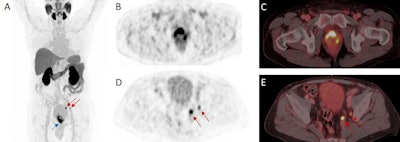

One well-documented limitation of PSMA-targeting radiotracers such as Ga-68 PSMA-11 and F-18 DCFPyL, however, is a high retention in the urinary system and especially high accumulation in the bladder, the researchers stated.

In this study, F-18 rhPSMA-7.3 showed low urinary retention and high uptake of tumor lesions resulting in a favorable tumor-to-bladder ratio, which could potentially increase the detection of local tumor deposits especially in the prostate base, they added.